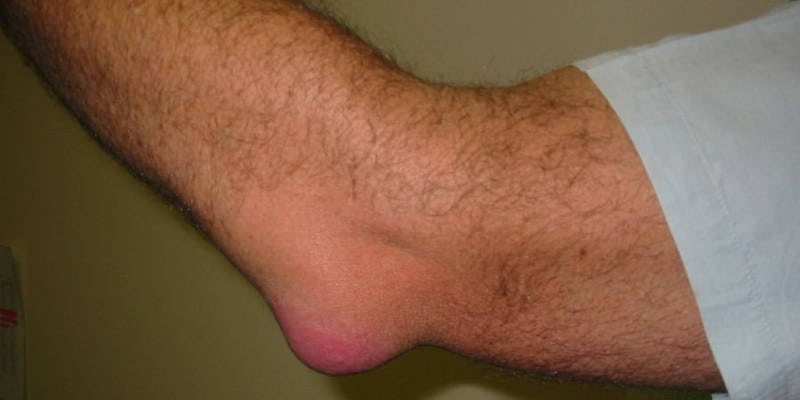

| Бурсит | Суставная сумка, расположенная в области наружной поверхности локтя | Наличие выраженной припухлости на наружной поверхности локтевого сустава | Бурситом болеют в основном мужчины молодого и среднего возраста |

На фото вы можете увидеть разные варианты воспаления локтевого сустава.

Локтевой бурсит

Бурсит, развившийся после легкого ушиба, обычно проходит самостоятельно. Ускорить выздоровление можно путем временной иммобилизации локтя и прикладывания компрессов с Димексидом. В случае выраженного воспаления больному назначают препараты из группы НПВС (Диклофенак, Нимесил, Ибупрофен).